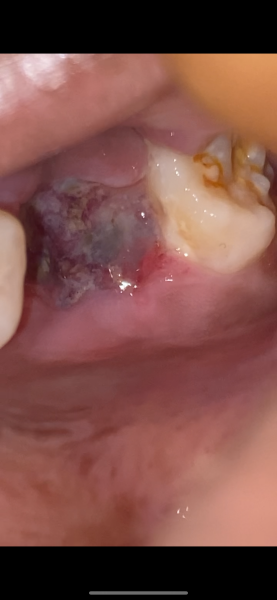

I would like to know if my tooth is healing properly I’m scared I may have a dry socket

This is what my tooth extraction site look like

Tooth extraction